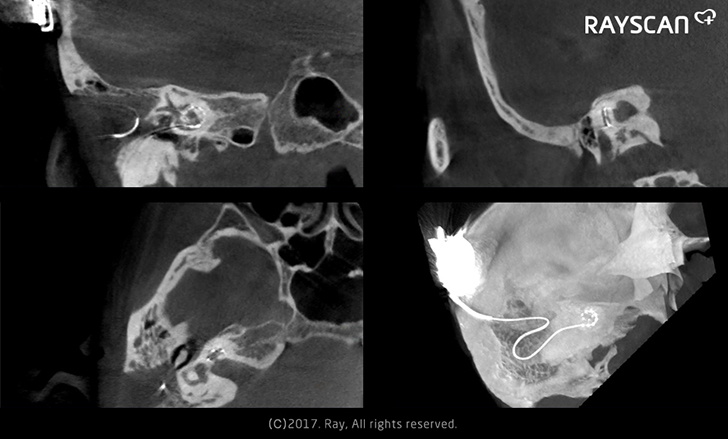

You can use our RAYSCAN m+ for more various applications than expected with its sharp CT images. For instance, it enables...

What best differentiates our RAYSCAN m+ from the other dental CBCTs is its extended usage for medical purposes. The large-sized DR...

The clear 3D images from RAYSCAN m+ visualize detailed morphological information from patients’ sinus, ear, airway, bones and soft tissues. The...

RAYSCAN m+ is the unique 2-in-1 imaging solution, combining Cone Beam CT and Digital Radiography, especially designed for otorhinolaryngology and plastic...